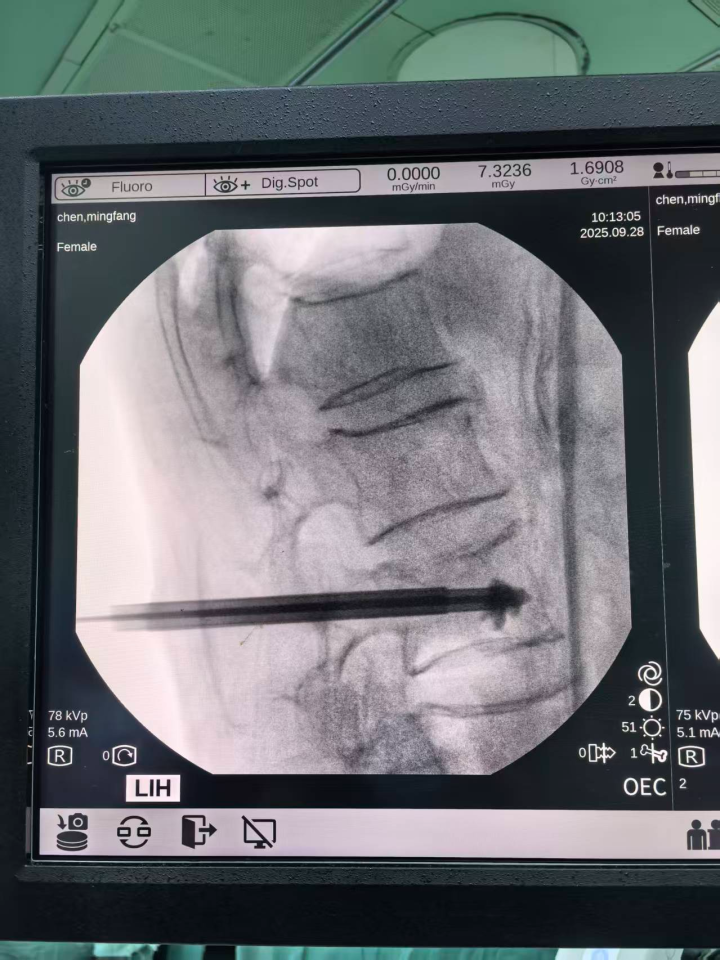

“面对老人骨头变形、放射线定位不清的问题,机器人精准定位能力凸显;针对骨头硬化难穿刺的情况,机器人有效避免了穿刺滑动、位置偏移。” 该院骨伤科四病区主任周昌伟介绍,在机器人辅助下,手术顺利完成,还减少了患者损伤、辐射暴露和手术时间,老人术后恢复良好。

传统手术依赖C臂定位,仅定位阶段就需反复照正侧位至少20多次,医生和患者均面临较多辐射暴露,而机器人辅助定位仅需6~7次,辐射量减少非常多,有效保障了医护人员和患者的健康安全。

传统手术中,医生需反复调整进针点及上下左右等三维方向,操作难度较大,机器人可实现毫米级精度定位,一次即可精准到位,医生只需按定位直接操作,无需反复调整,大幅降低了操作难度。